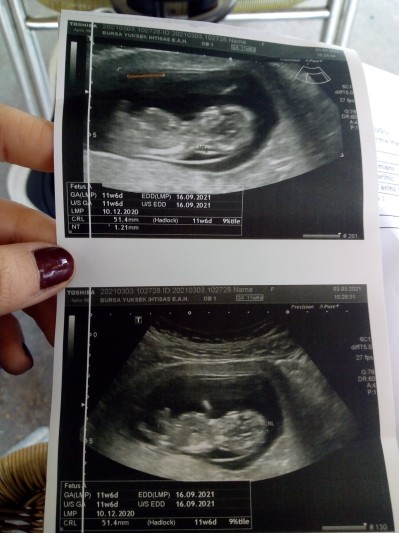

Arkadaşlar biliyorum böyle şeyler hurafe fakat yine De merak ettim ne gibi gözüküyor fikirlerinizi alabilir miyim 11+7

Gebelik haftası 11+7